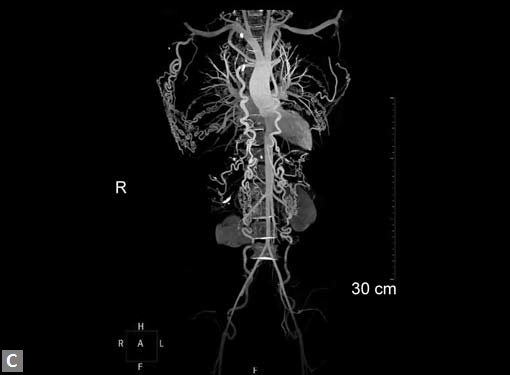

Any part of aorta can get affected by aneurysms. Focal

dilations can be saccular or fusiform. Atherosclerosis is

the most common cause. Tubercular and other infective

aneurysms, traumatic ones are also uncommonly seen. Size

of the aneurysm, proximity to origin of main vessels, relation

with branching and bifurcation, presence of mural thrombus

are the critical information sought on CT.

Contained leak, rupture are the feared complications.

Aortoenteric fistula is a rare but potentially catastrophic

complication. Aneurysmal dilation is common in ascending

aorta (Figs 19W to Y).

CT is also useful in surveillance of diagnosed aneurysms.

Figs 19A to Y (A to C) Scannogram (A), plain (B) and contrast study (C) show partial anomalous pulmonary venous connection; (D to F) Heterotaxy; (G) Aortic occlusion; (H and I) Aortic stents; (J) Aortic dissection with ‘Benz’ sign due to second dissection within the true lumen; (K, L and M) Aortic dissection with thrombus in pseudolumen following catheter angiogram; (N) Aortic dissection involving common carotid arteries and subclavian artery; (O, P, Q and R) Aortic dissection with right renal artery arising from true lumen and left renal artery from false lumen; (S, T, U and V) Stanford B dissection with extension Y to iliac vessels; (W to Y) Aneurysmal dilation of ascending aorta

CT is also useful to diagnose restenosis or aneurysm at the site of repair following surgical repair of aortic coarctation or interruption. CT is the modality of choice in investigating stent and associated complications. It is used to confirm patency of stent, to diagnose stenosis, occlusion, thrombus, fracture and stent separation from vessel wall. Residual vessel narrowing and pseudo aneurysm can be diagnosed.